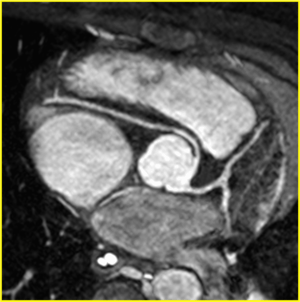

| Anomalous origin of the right coronary artery from the left coronary sinus by CMR with an inter-arterial, potentially dangerous course | |